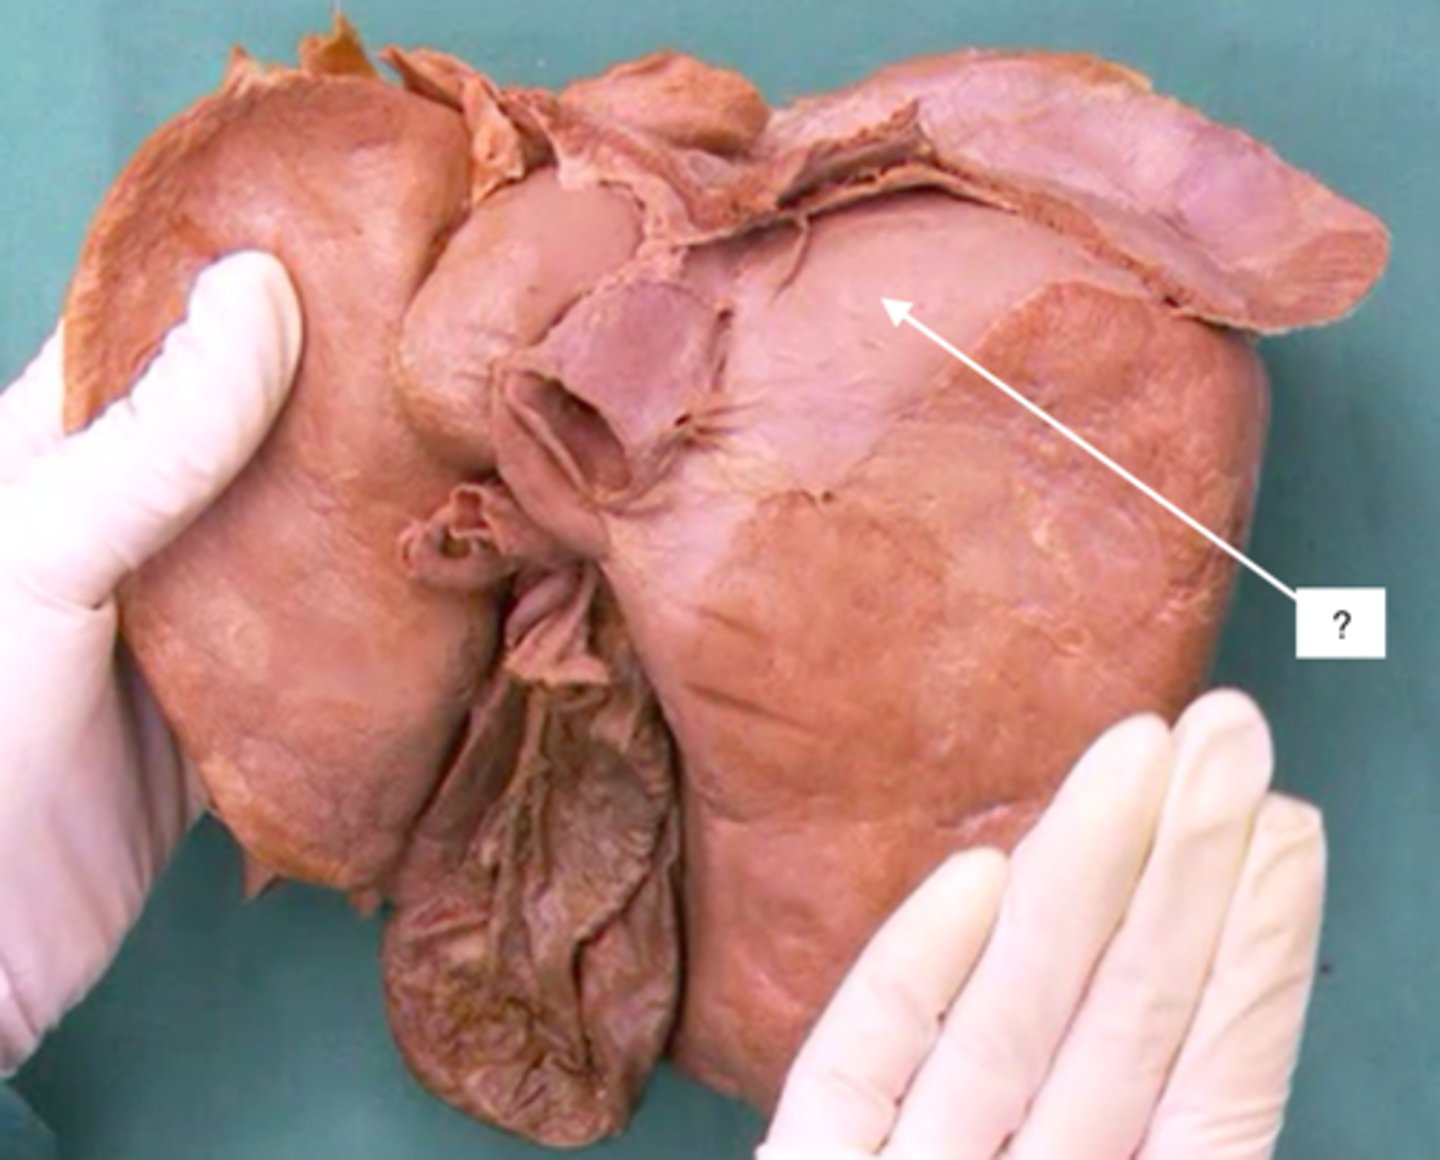

hepatoduodenal ligament

portal triad

what is in this structure